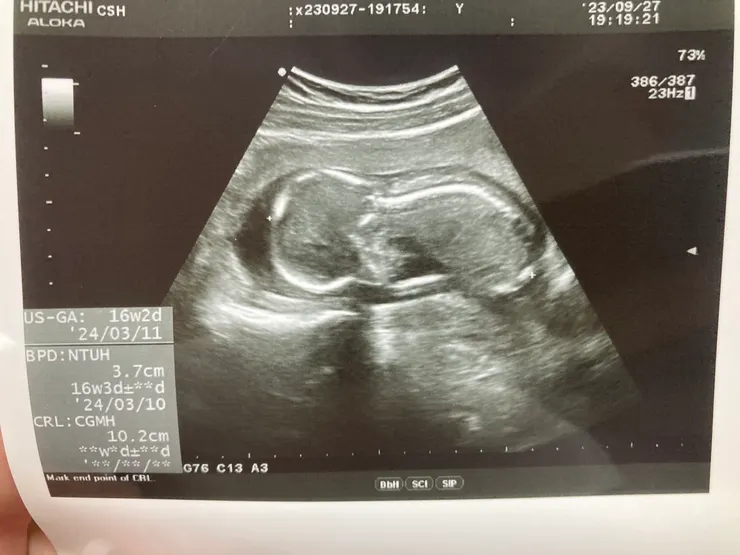

16W 的小幅氣

這個月最期待的就是要去看小福氣的性別,朋友們一直鼓吹我們要辦性別趴,但媽媽很懶!? 但總之在最後一刻,跟醫生說幫我們保密吧!!!結果寶寶本人不想開獎,直接給我們一個嬰兒式的趴姿結束這回合! ㄟ~ 媽媽排隊等很久結果照一下就結束了@@每次我都覺得別人看診很久輪到自己卻五分鐘結束!!不過醫生說,最美的就是看到小福氣完整的脊椎!是不是可可愛愛呢~我的孩子真可愛呀~~~